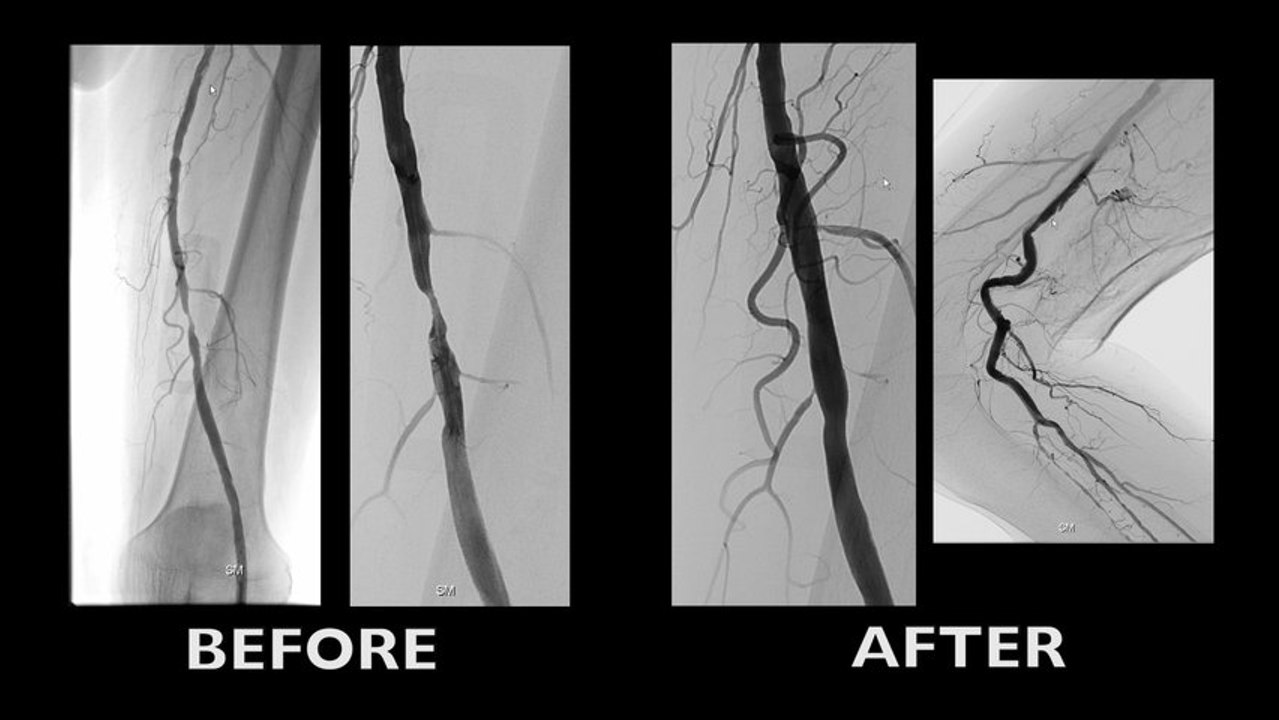

PAD is moving distally

Obstructive disease pattern in CLI

To recognize the role of small vessel disease in critical limb ischemia

Distality matters

Unmet clinical needs in BTK